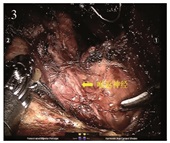

目的  探讨在达芬奇机器人甲状腺癌根治术中应用纳米碳示踪剂对淋巴结清扫及甲状旁腺、喉返神经保护的作用。

方法  收集实施达芬奇机器人甲状腺乳头状癌根治术的60例患者资料,按照随机对照的方法分为研究组(30例)和对照组(30例),对照组行常规达芬奇甲状腺癌根治术,研究组术中加用纳米碳示踪剂。对两者术后Ⅵ区淋巴结清扫总数及阳性数目、血钙、PTH水平、低钙血症发生率、甲状旁腺功能减退发生率、甲状旁腺误切率、喉返神经损伤发生率进行比较。

结果  研究组和对照组Ⅵ区总淋巴结检出数分别为247和173枚(Z=-2.228, P=0.026),阳性淋巴结检出数分别为99和65枚(Z=-1.986, P=0.047);两组术后第1、2天血钙及PTH水平均较术前1天下降,但研究组术后第1、2天血钙及PTH水平较对照组高,差异有统计学意义(P < 0.05);两组术后暂时性甲状旁腺功能减退分别为4例(13.3%)和11例(36.7%),差异有统计学意义(P < 0.05)。

结论  在达芬奇机器人甲状腺癌根治术中应用纳米碳示踪剂可以更好清扫Ⅵ区淋巴结,同时能有效保护甲状旁腺,但对喉返神经无肯定保护作用。